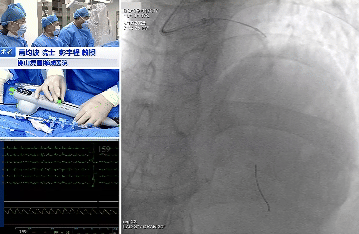

手术过程:

术中造影

OAS处理前降支

术中造影提示第一、第二对角支开口严重狭窄,分别对前降支严重钙化病变、回旋支次全闭塞应用OAS进行旋磨等充分预处理后,导丝顺利通过病变,成功植入支架、药物球囊,实现血管再通,术后患者血流恢复良好。